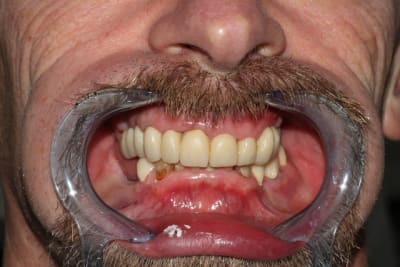

Bon allez, du coup je me lance.

Encore une fois, plusieurs décisions sont critiquables, et j'avais au moins 10 possibilités en tête pour le bonhomme. (et sur des cas comme ça, en comparaison de ce que font certains ici, je me sens tout petit, mais bon...)

En l’occurrence, 2 devis proposés: un amovible, minimum: extractions multiples, refaire ce qui doit l'être d'urgence et stellite haut et bas; et un tout fixe.

Le patient réfléchit, revient 3 mois plus tard: ok pour le fixe, boulot commencé en septembre.

En prévision: bridge complet 16-26 en haut (extension en 26), bridge secteur 3 en bas, implants 45 46.

En tout, boulot réalisé sur une quinzaine de séances, contrôles et réglages inclus.

Au départ, je pensais extraire 17,12 et 23.

La paro a été gérée "en continu", tout du long: détartrages supra gingivaux et irrigations éventuelles à chaque séance. L'hygiène est parfaitement suivie du début à la fin.

Première séance de préparation: ex 17, dépose des couronnes sans antagonistes pour se faciliter un peu le boulot de la deuxième séance, empreintes primaires.

Deuxième séance, 2h30 si mes souvenirs sont bons: préparations de tout le maxillaire, et pose du bridge pro avec une DV remontée de quelques mm. DSR manuel des poches profondes, curetage rotatif à la touati de toutes les préparations, l'accès visuel est largement simplifié.

La 12 est finalement conservée, la 24 finalement extraite.

Petit imprévu: impossible de sortir la 23, trop délabrée: je ne me sens pas de lever un lambeau lors de cette séance déjà longue, on la laisse en place pour l'instant.

Contrôle 2 jours plus tard, la nouvelle DV est bien supportée.

Les courbes occluasles ne sont pas alors idéalisées (la 36 gêne, et secteur 1 on la règlera à la plaque de fox par la suite)